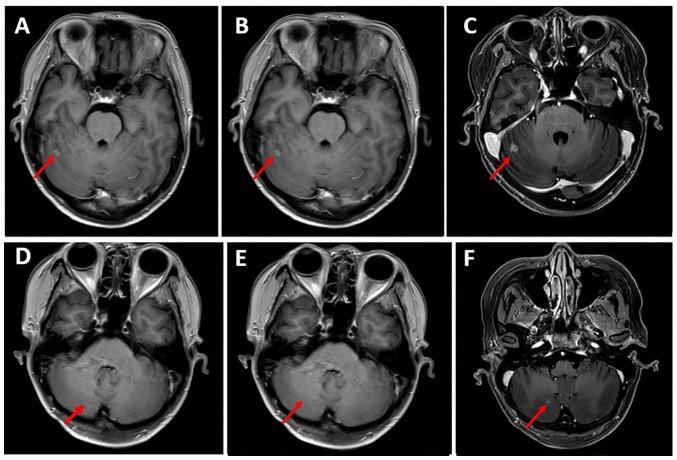

For patients with hormone receptor-positive (HR) and human epidermal growth factor receptor 2-negative (HER2) metastatic breast cancer (mBC), the treatment choices become more complex after progression on first-line CDK4/6 inhibitors combined with endocrine therapy. Currently, there are no guidelines that provide a unified standard protocol for this situation. Almost half of patients with mBC develop brain metastases (BMs), and once BMs occur, the survival of the patient is often significantly reduced. An anti-angiogenic drug and chemotherapy combination of has demonstrated synergistic effects in an mBC cell line. Anti-angiogenic drugs have shown therapeutic efficacy in the treatment of mBC, and utidelone has shown the ability to cross the blood-brain barrier and achieve a high concentration in brain tissue in preclinical studies. The present case report describes a patient with HR/HER2 mBC and BMs that developed resistance to two CDK4/6 inhibitors and treatments with anthracyclines/taxanes. The patient received a fourth-line treatment regimen combining utidelone with a small-molecule anti-angiogenic drug, namely apatinib or anlotinib. The patient achieved a partial response with this combined regimen, and a progression-free survival (PFS) of 7.6 months, which was the best therapeutic outcome in the entire course of the illness. This result was superior to the second-line treatment with nab-paclitaxel, which resulted in a PFS of 8 months and best overall response of stable disease with slight shrinkage. The present case indicates that a combination of utidelone with apatinib/anlotinib exhibited antitumor activity in a patient with HR/HER2 mBC with BMs. Therefore, this combination offers a promising therapeutic option for the clinical treatment of patients with breast cancer and BMs.

对于激素受体阳性(HR)且人表皮生长因子受体2阴性(HER2)的转移性乳腺癌(mBC)患者,在一线CDK4/6抑制剂联合内分泌治疗进展后,治疗选择变得更加复杂。目前,尚无指南针对这种情况提供统一的标准方案。几乎一半的mBC患者会发生脑转移(BMs),一旦发生BMs,患者的生存期通常会显著缩短。抗血管生成药物与化疗联合在一种mBC细胞系中已显示出协同作用。抗血管生成药物在mBC治疗中已显示出治疗效果,在临床前研究中,优替德隆已显示出能够穿过血脑屏障并在脑组织中达到高浓度。本病例报告描述了一名患有HR/HER2 mBC和BMs的患者,该患者对两种CDK4/6抑制剂以及蒽环类/紫杉类治疗产生了耐药性。该患者接受了优替德隆与小分子抗血管生成药物(即阿帕替尼或安罗替尼)联合的四线治疗方案。该联合方案使患者获得了部分缓解,无进展生存期(PFS)为7.6个月,这是整个病程中的最佳治疗结果。该结果优于二线白蛋白结合型紫杉醇治疗,后者的PFS为8个月,最佳总体反应为疾病稳定且有轻微缩小。本病例表明,优替德隆与阿帕替尼/安罗替尼联合在一名患有HR/HER2 mBC和BMs的患者中表现出抗肿瘤活性。因此,这种联合为乳腺癌和BMs患者的临床治疗提供了一种有前景的治疗选择。